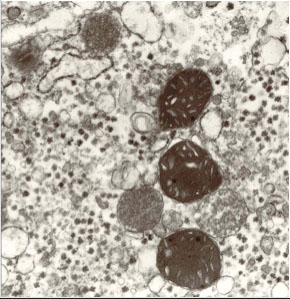

EM: funny mitochondria and fish mouth canaliculi

Funny mitochondria and fish mouth canaliculi in Wilson's